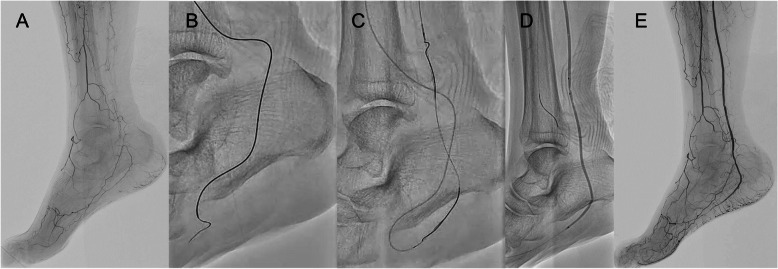

Background: Endovascular therapy (EVT) has become a key revascularization strategy for patients with chronic limb-threatening ischemia (CLTI), especially in cases involving infrapopliteal (IP) chronic total occlusions (CTOs), which are often challenging to treat using standard antegrade approaches alone. Trans-collateral angioplasty (TCA) is a retrograde technique that accesses the distal true lumen via collateral vessels when conventional methods are unsuccessful. However, clinical evidence regarding the efficacy and safety of TCA remains insufficient. This study aimed to evaluate the efficacy and safety of TCA as a retrograde approach during EVT for IP CTO lesions.

Results: This retrospective single-center study included 44 IP CTO lesions in patients who underwent TCA between January 2020 and December 2022, after excluding 18 lesions treated solely with the pedal-plantar loop technique. The mean patient age was 78.8 years, and 81.8% had diabetes, 79.5% had chronic kidney disease, and 31.8% were on dialysis. EVT success was achieved in 95.5% (95% CI: 84.9-98.7) of lesions. TCA alone achieved lesion crossing in 70.5% (95% CI: 55.8-81.8), while distal puncture was required in 13.6% (95% CI: 6.4-27.0) of cases. Various crossing techniques, including the rendezvous technique and reverse subintimal tracking, were conducted. Collateral vessel-related complications occurred in 11.3% (5 lesions; 95% CI: 5.0-24.6), including injury in 6.8%, and occlusion and spasm in 2.3%. No vessel dissections occurred. The overall incidence of perioperative complications within 30 days was 20.5% (95% CI: 11.3-34.2), most commonly gastrointestinal bleeding and stroke. At one year, the rate of freedom from target lesion revascularization was 45.4%, and amputation-free survival was 84.0%.

Conclusions: Our findings suggest that TCA can be a feasible and relatively safe retrograde strategy for complex IP CTO lesions when antegrade wiring fails. It is associated with high procedural success and a low incidence of collateral vessel-related complications, supporting its use in selected cases of CLTI.